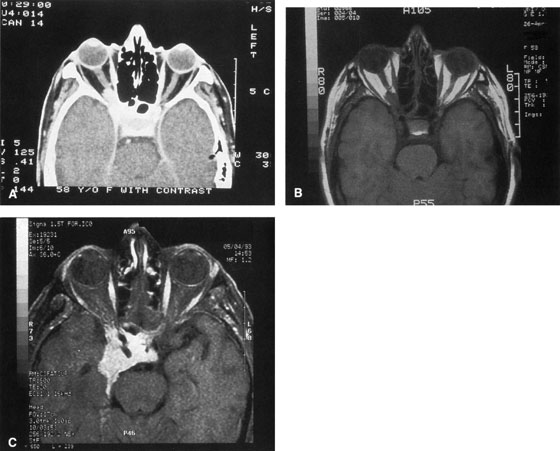

Figure 10. A. Large, well-encapsulated intraconal mass on MR scan. B. Small lateral canthotomy incision will be used to perform lateral orbitotomy and remove the intraconal mass.

Fig. 11. A. Lateral canthotomy incision is made with straight iris scissors. B. Periosteum is elevated off of the lateral orbital rim. C. Wide undermining allows retraction of the skin incision to permit superior and inferior osteotomies to be made with the air-driven saw. D. The bony rim has been outfractured. Because of the distensibility of the skin, it is possible to remove a large bone flap through the small canthotomy incision. E. The intraconal mass is extracted with the aid of the cryoprobe. F. The bone fragment is positioned for resuturing.

Fig. 12. A. The lateral canthotomy incision is reapproximated with simple closure of the superior and inferior crura of the lateral canthal tendon. A drain from the temporal fossa has been brought out through a separate stab incision posteriorly. 12B. Excellent postoperative scar camouflage is obtained by this approach.